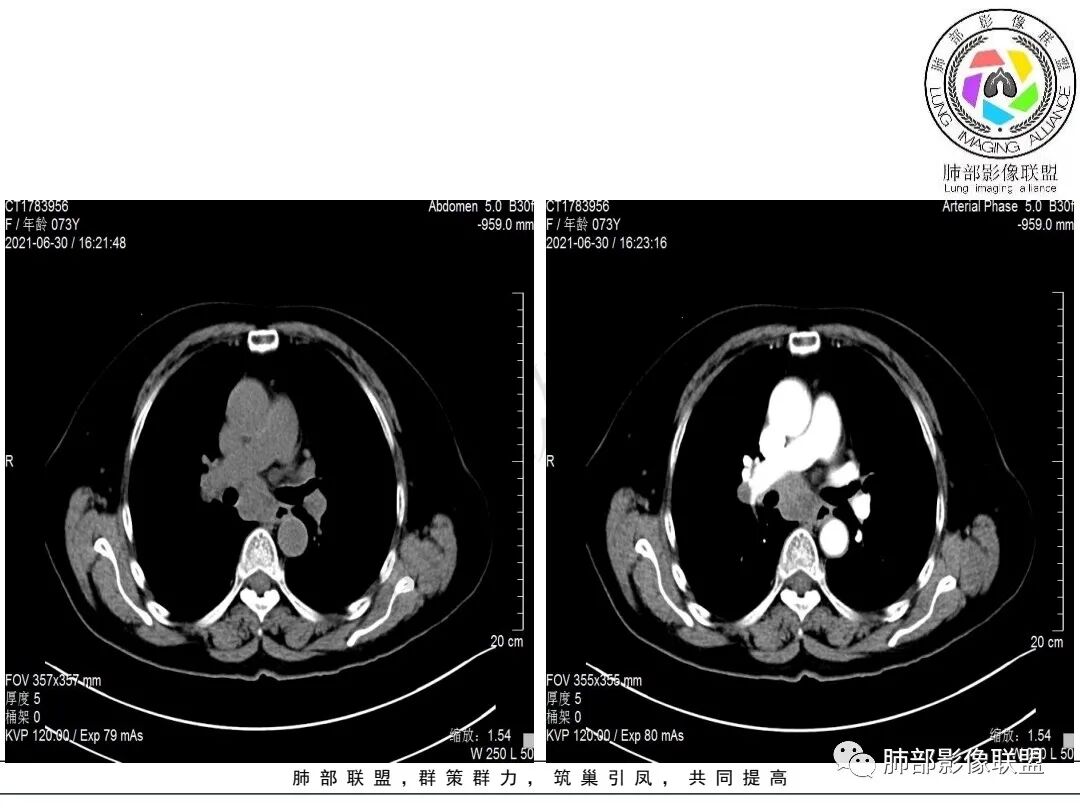

1.老年女性,咳嗽两月。CEA,T-spot阴性。

2.右肺下叶不规则实性密度块影,占据外后基底段及背段较大范围,可见轻度分叶、毛刺及棘状突起,未见明显胸膜牵拉及凹陷。

3.右肺下叶支气管轻度狭窄,病灶内见部分充气支气管征,外后基底段不能连续跟踪。

轻度不均匀强化,病灶内小血管显示不满意,未见明确坏死区。

4.右肺门及纵隔见多处增大淋巴结,不均匀环形强化,后下纵隔(隆突下)肿大淋巴结十分显眼!